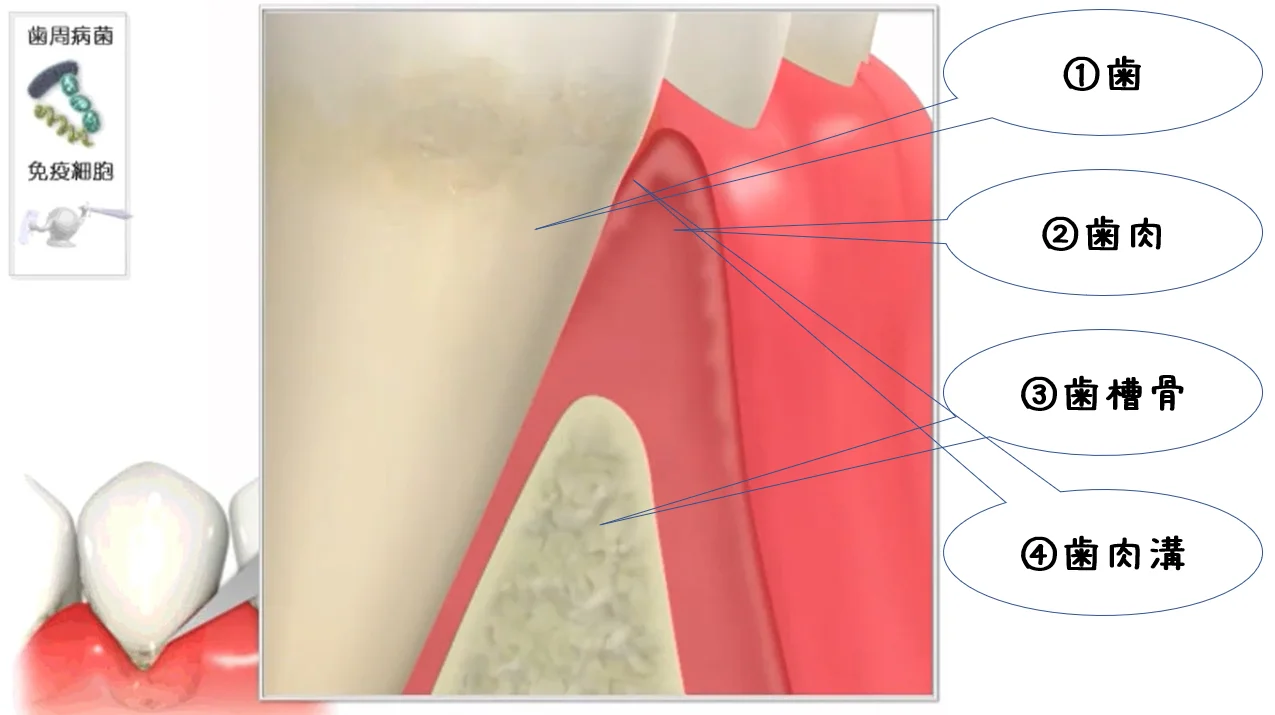

Q&A~歯周病ってなに?②~

こんにちは。 今回は前回に引き続き、歯周病について書いていきたいと思います。 思った以上のボリュームで、一気には書けませんでしたからね・・・(;'∀') 前回までのあらすじ ~プラークが付着し続けると、炎症が長引き歯肉の接着が外れて、歯周病…

Q&A~歯周病ってなに?①~

こんにちは。 今日はテレビや雑誌などでも耳にする機会の多い「歯周病」について書いていきたいと思います。 とはいえ、1回で書ききれるものではないので、そもそもの病態というか、その進み方を書いていきます。 ちなみに、進み方だけでも、すっごい長く…

続きを読む →